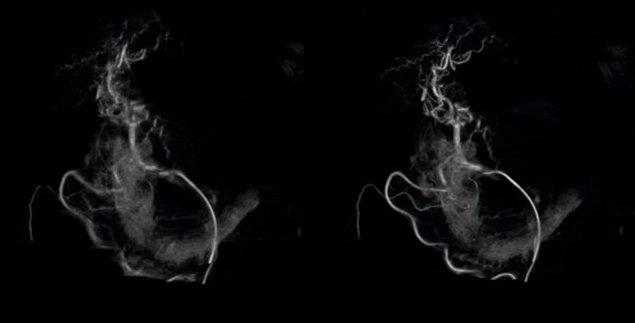

Bildquelle: Siemens Healthineers; Bild mit freundlicher Genehmigung von Stanford Hospital and Clinics, USA

Auch für die Embolisation – einem minimalinvasiven Verfahren, bei dem die Blutversorgung eines Tumors blockiert oder Medikamente gezielt an tumorversorgende Gefäße abgegeben werden – hat Siemens Healthineers eine spezielle KI-Lösung entwickelt. Der organspezifisch trainierte Algorithmus unterstützt interventionelle Radiologen bei Planung und Navigation. Verfügbar sind Workflows für Leber, Prostata und ein allgemeiner Modus.

Der Leber-Workflow bietet eine dreidimensionale Tumorkonturierung mit klar definierten Behandlungszonen. Die integrierte Gefäßkarte unterscheidet automatisch zwischen tumorversorgenden und anderen Gefäßen – eine Funktion, die laut Prof. Dr. Frank K. Wacker, Präsident der Deutschen Gesellschaft für Interventionelle Radiologie (DeGIR), nicht nur die Präzision erhöht, sondern auch die Ausbildung junger Assistenzärzte verbessert: „Jede Orientierungshilfe im Arbeitsablauf verbessert das Lernerlebnis erheblich."